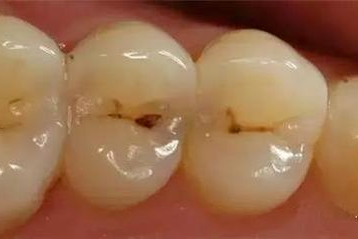

龋齿形成的四个阶段